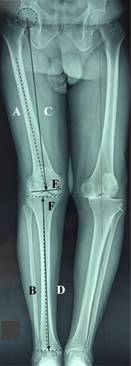

To achieve this post-surgical alignment it is necessary to remember all of the measurements to be included in preoperative planning.2,3,4,5,6,7,8,9,10,11 Initially, we must identify the center of the femoral head, the joint center of the distal femur (JCDF),12,13 the joint center of the proximal tibia, and the joint center of the ankle (Figure 1);14 which will allow us to draw the following axes: femoral anatomical axis (FAA), tibial anatomical axis, femoral mechanical axis (FMA), tibial mechanical axis, distal femoral osteotomy (DFO) line and tibial joint line (Figure 2). The line to connect the center of the femoral head to the joint center of the ankle is named the load axis, mechanical axis, or Maquet line.15,16,17

Figure 2:Preoperative planning axes. A) Femoral anatomical axis, B) tibial anatomical axis, C) femoral mechanical axis, D) tibial mechanical axis, E) distal femoral osteotomy (perpendicular line to femoral mechanical axis), F) tibial joint line (dotted line- In this case is not perpendicular to tibial mechanical axis).

To make a distal femoral osteotomy completely perpendicular to the femoral mechanical axis (a DFO with 90o to FMA) we calculate the angle between FMA and FAA (Figure 2).2,7 But if we have an extra-articular deformity (EAD), meaning a femoral or tibial angulation located at 5 cm proximal or distal to the knee joint line,2,18,19 outcomes are going to be different and the likelihood of achieving the correct post-surgical alignment will be decreased. The problem is more critical on the femoral side because the endo-medullar guide can change its position by hitting the cortical bone and thereby changing the DFO and the final alignment. On the tibial side the extramedullary guide allows us to make any correction that is needed.18,18,20,21 You can achieve a successful intra-articular correction (IAC) if the deformity does not exceed the coronal plane by 20o at the femur or 30o at the tibia.2,18,22